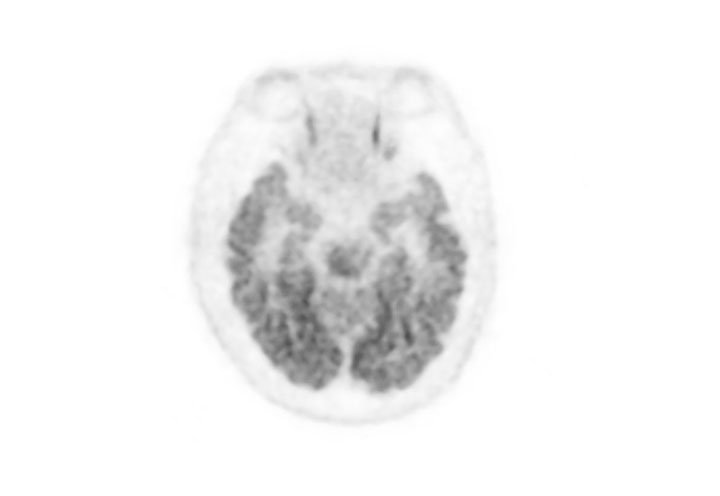

Head / Case2 : FDG

Courtesy : Kindai University Hospital

- Imaging protocol

- Injected dose: 3.29 MBq/kg, 18F-FDG

- Uptake time: 38 minutes

- Scan time: 30 minutes